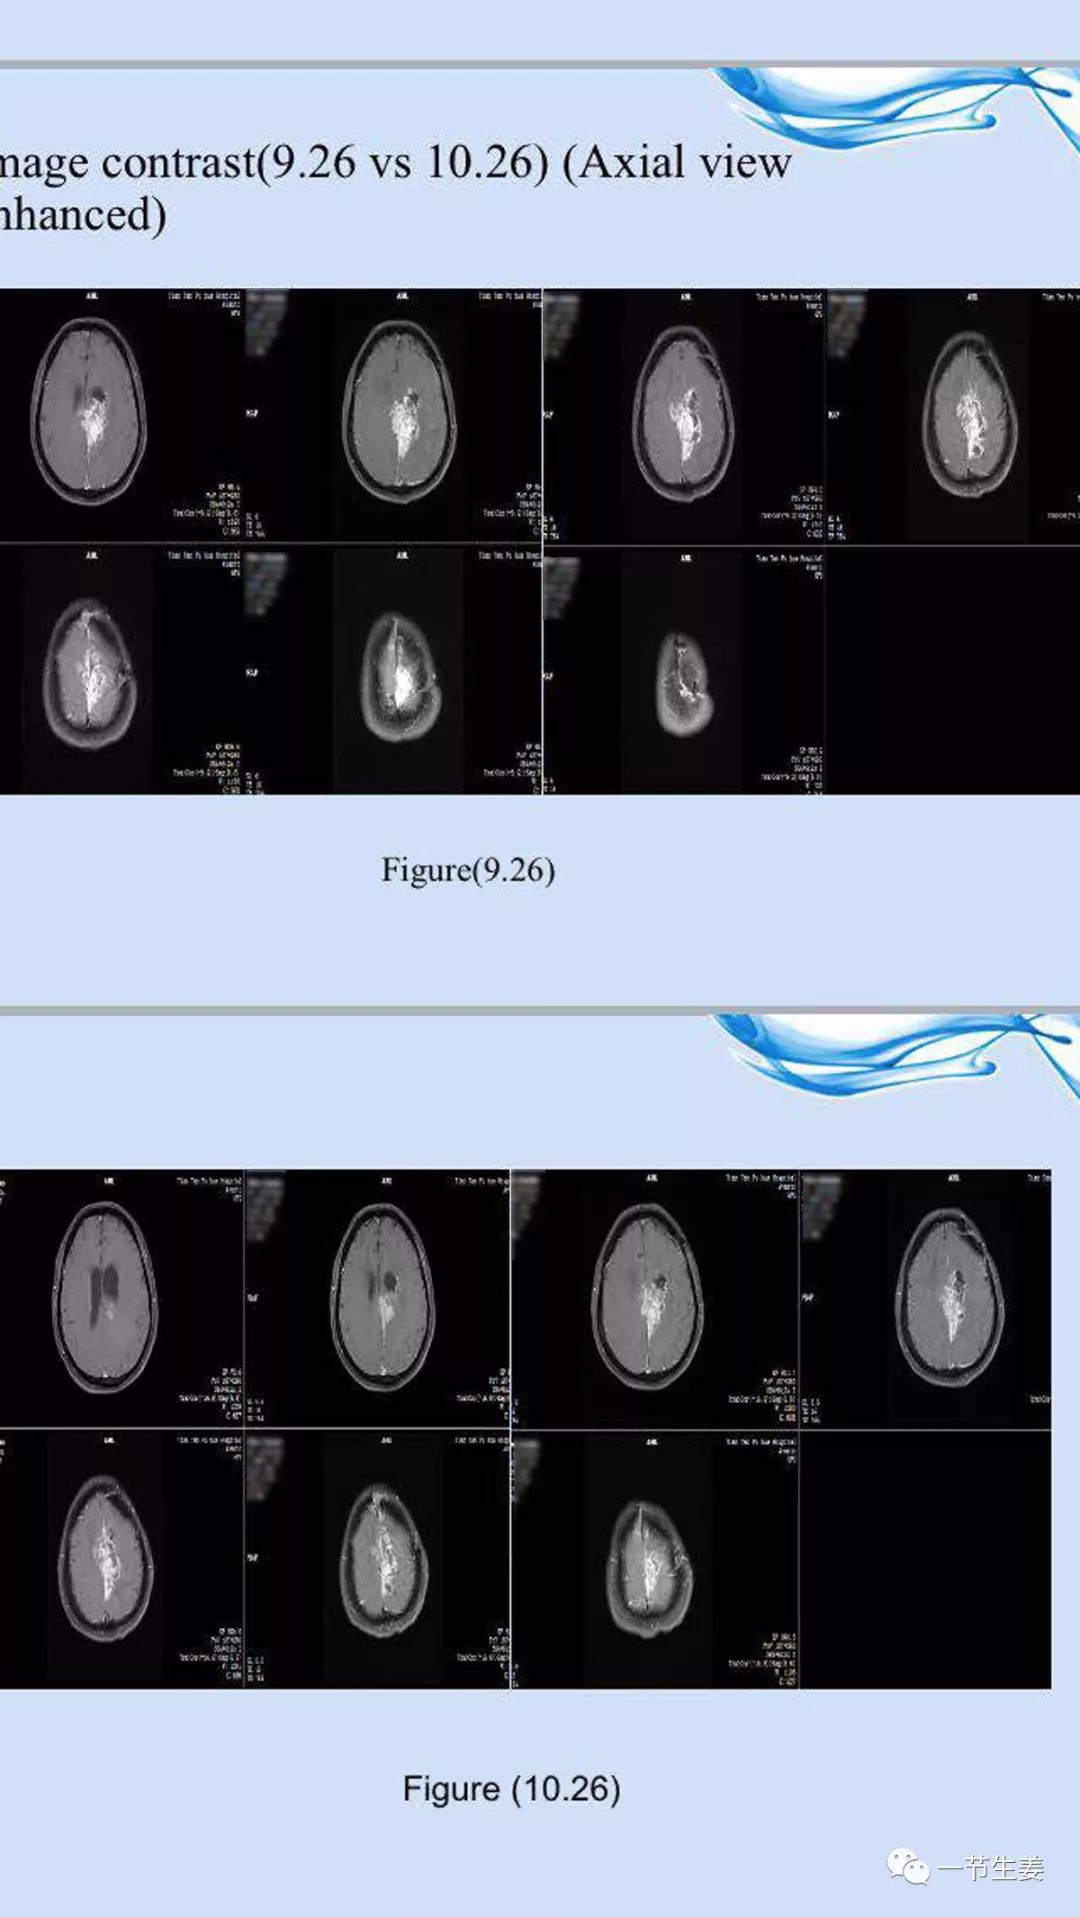

陆伟终于用上了TTF。使用一个月后复查,增强核磁 扫描显示脑部病变有所缓解(见下图)!陆伟又继续使用了两个月的穿戴设备,复查显示病情稳定。

图:陆伟使用TTF治疗前后的增强核磁结果比较。上图(9.26)为治疗前,下图(10.26)为治疗后。

虽然增强核磁显示有好转,但是肿瘤并没有消失,病情稳定,不要恶化,就是目前最好的希望。